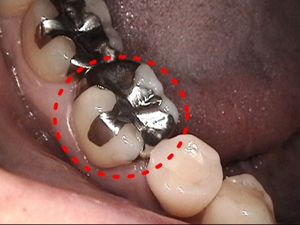

1. 患歯の切削

治療箇所を削ります。金属が入っていた部分をやり替える場合は外して形を整えます。